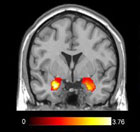

A new study reveals a simple strategy that people can use to minimize how angry and aggressive they get when they are provoked by others. When someone makes you angry, try to pretend you are viewing the scene at a distance – in other words, you are an observer rather than a participant in this […]